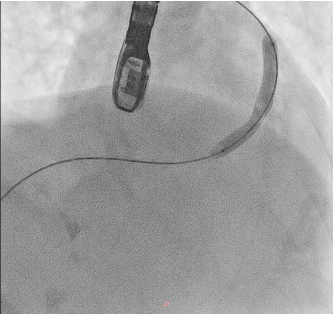

A soft hydrophilic 0.035-inch wire was directed into the RVOT, advanced distally to the right pulmonary artery, then exchanged for a super stiff 0.035-inch wire. An Armada vascular balloon 7.0x60 mm was positioned in the RVOT and inflated to 12 atm for ten cycles. An Omnilink vascular stent was deployed in the RVOT and inflated to 12 atm. Due to the patient¡¯s late presentation, a second identical stent was placed at the same location. Following the procedure, LVEF improved to 64.7%, and aortic oxygen saturation increased from 86% to 94%.